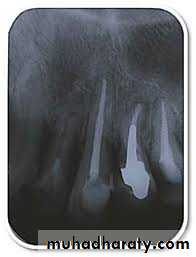

EXTRARADICULAR INFECTIONSExtraradicular infection in turn is characterized by microbial invasion of the inflamed periradicular tissues and is a sequel to the intraradicular infection. Extraradicular infections can be dependent on or independent of the intraradicular infection

In most situations, apical periodontitis inflammatory lesions succeed in preventing microorganisms from invading the periradicular tissues

Nevertheless, in some specific circumstances, microorganisms can overcome this defense barrier and establish an extraradicular infection. The most common form of extraradicular infection is the acute apical abscess, characterized by purulent inflammation in the periradicular tissues in response to a massive egress of virulent bacteria from the root canal

There are, however, other forms of extraradicular infection either by adherence to the apical

external root surface in the form of extraradicular biofilm structures or by formation of cohesive actinomycotic colonies within the body of the inflammatory lesion